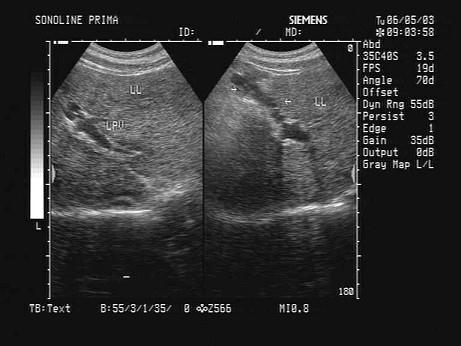

问题 某患者肝脏声像图表现如图,提示肝脏回声不均匀致密,肝内可见一管状结构,诊断为?(?)

选项 A.肝内胆管扩张 B.肝淤血 C.脐静脉重开 D.肝血管瘤 E.门脉海棉样变性

答案 C